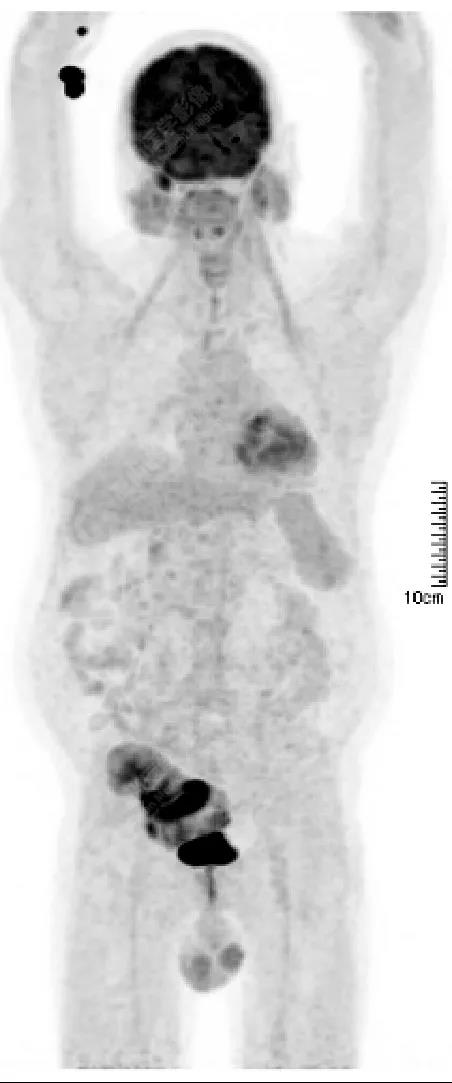

PET/CT檢查

↑移植腎下部等密度腫塊,代謝環(huán)狀增高,SUVmax13.4,中心代謝缺損

發(fā)現(xiàn)全身其它部位有無結(jié)內(nèi)或結(jié)外淋巴瘤病灶。由于淋巴瘤組織多具備高代謝、大范圍無氧酵解的特性,葡萄糖需求量為正常組織細(xì)胞的20~30倍,正電子湮滅產(chǎn)生的光子信號聚集于灶區(qū),PET捕獲后可半定量分析其分布特征【4】。

PET/CT融合二者各自優(yōu)勢

將影像學(xué)技術(shù)提高到分子水平,結(jié)合以腫瘤形態(tài)學(xué)、解剖學(xué)、代謝學(xué)特征,對DLBCL細(xì)胞增殖、生長或凋亡可作出有效判斷,還可為檢驗治療有效性與預(yù)后療法優(yōu)化提供指導(dǎo)【4】。